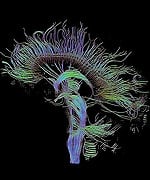

"Science now has the ability to map the entire brain, and we now know exactly where growth hormone works on mood, which pathways it uses," says Dr. Gordon. "The military is simply not prepared to go to the depths that we have in the private sector." Patients typically respond within weeks to the Millennium approach. And the responses tend to be dramatic. Gordon recalls one case in particular, of a woman who had been involved in a "T-bone" car crash - a notoriously deadly situation in which the victim's vehicle is hit full-force from the side. The patient was left with multiple neurological deficits. She spoke with a stutter and needed to keep one hand on the wall as she walked in order to maintain her balance. She had substantial memory impairment as well. After a series of blood tests, Dr. Gordon began administering small doses of the hormones that were deficient in this patient's case. She soon showed encouraging progress, with diminished speech and balance impairment. Gordon recalls with obvious delight, "One day about six months later, I got a phone call from a woman who said, in a perfectly normal voice, ‘Hi, this is your patient Nancy.' I told her to stop joking and asked who it was. ‘I'm your patient, Nancy, the one with the bad stutter. I woke up this morning, and this is how I was able to speak. I just wanted to let you know.'" Nancy's case, though dramatic, is far from unique. Since that time, Dr. Gordon has treated scores of other patients with similar outcomes, which is why military veterans coming to him are in good hands: he has obtained a grant from Access Medical Laboratories in Jupiter, Florida, which currently covers the cost of testing veterans with traumatic brain injury. "They've arranged for a phlebotomy company to go to the veterans' homes and draw blood. Lab tests use a spectrum that goes way beyond typical blood tests, providing a bigger database." Any treatment starts with baseline hormone testing of testosterone, growth hormone, thyroid, and cortisol.

Growth Hormone: A Critical PlayerGrowth hormone is the most common hormone deficiency or insufficiency in patients with traumatic brain injury at any level of severity.16-19 Deficiencies in this hormone are especially marked in patients with moderate to severe traumatic brain injury.20 Brain-injured patients with growth hormone deficiency experience rapid weight gain and have substantially lower levels of other hormones as well.17,19 Low growth hormone levels are also associated with excessive anxiety and depression and poor physical health and quality of life.15,21 Finally, brain-injured patients with growth hormone deficiency show greater deficits in attention, executive functioning, memory, and emotion than those with normal growth hormone levels.22 Growth hormone is an intriguing hormone, and we are learning more about it each year. In children, it is responsible for regulating linear growth, ultimately determining adult height and body proportions. But growth hormone has many other remarkable functions throughout the body and into adulthood. It is neuroprotective, increasing survival of damaged nerve cells and promoting regeneration of nerve tissue.23-25 Growth hormone also increases the number of receptors for other hormones in tissues throughout the body; this has the effect of increasing the body's sensitivity to those hormones' actions, helping to overcome the effects of their deficiencies.26-29 Like all hormones, growth hormone acts by binding to specific cell-surface receptors. Receptors for growth hormone are found throughout the brain, and they are especially densely distributed in brain regions responsible for learning and memory.30,31 That may explain why declining growth hormone levels are associated with poorer cognitive function. Growth hormone levels fall with age and are especially low in Alzheimer's disease.32-36 As Dr. Gordon points out, it is therefore not surprising that traumatic brain injury patients often show symptoms identical to the cognitive decline and memory loss we see with aging and Alzheimer's disease. In essence, a brain-injured patient with low growth hormone levels undergoes accelerated cognitive aging. Hope for Traumatic Brain Injury Patients at Millennium Health Centers